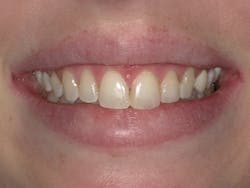

The patient was ecstatic with her new smile (figure 7). A five-year post-op photo shows stability of the result with no recurrence of the demineralized enamel (figure 8).